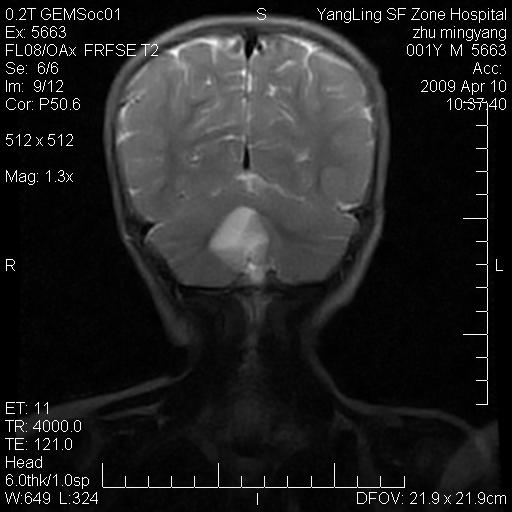

患者:1岁半,两天前外伤收住我院,ct检查小脑占位

考虑星形细胞瘤,建议增强

髓母细胞瘤或血管母细胞瘤,增强后可以鉴别;影像资料见 <。鱼博浪老师的《中枢神经系统ct与mr鉴别诊断》 小脑部肿瘤章节。

髓母细胞瘤或血管母细胞瘤!支持!

支持考虑髓母细胞瘤

考虑----髓母细胞瘤可能性大

考虑髓母细胞瘤或室管膜瘤。

支持髓母细胞瘤。

考虑髓母细胞瘤。

考虑髓母细胞瘤或星形细胞瘤

考虑髓母细胞瘤.

考虑髓母细胞瘤可能性大。

小脑肿瘤.考虑髓母细胞瘤可能.

就病灶部位及临床资料首先考虑髓母.